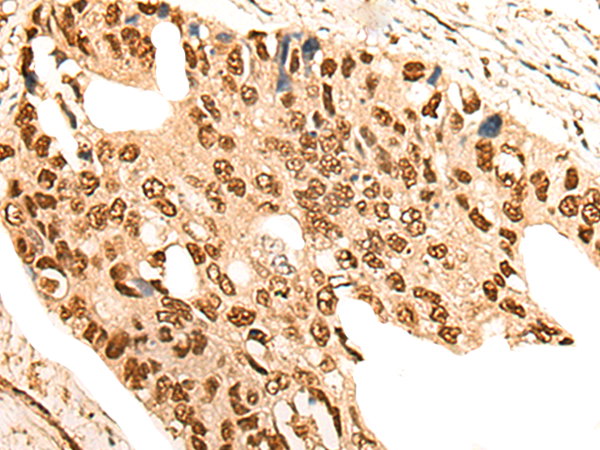

IHC positive control: |

Human prostate cancer |